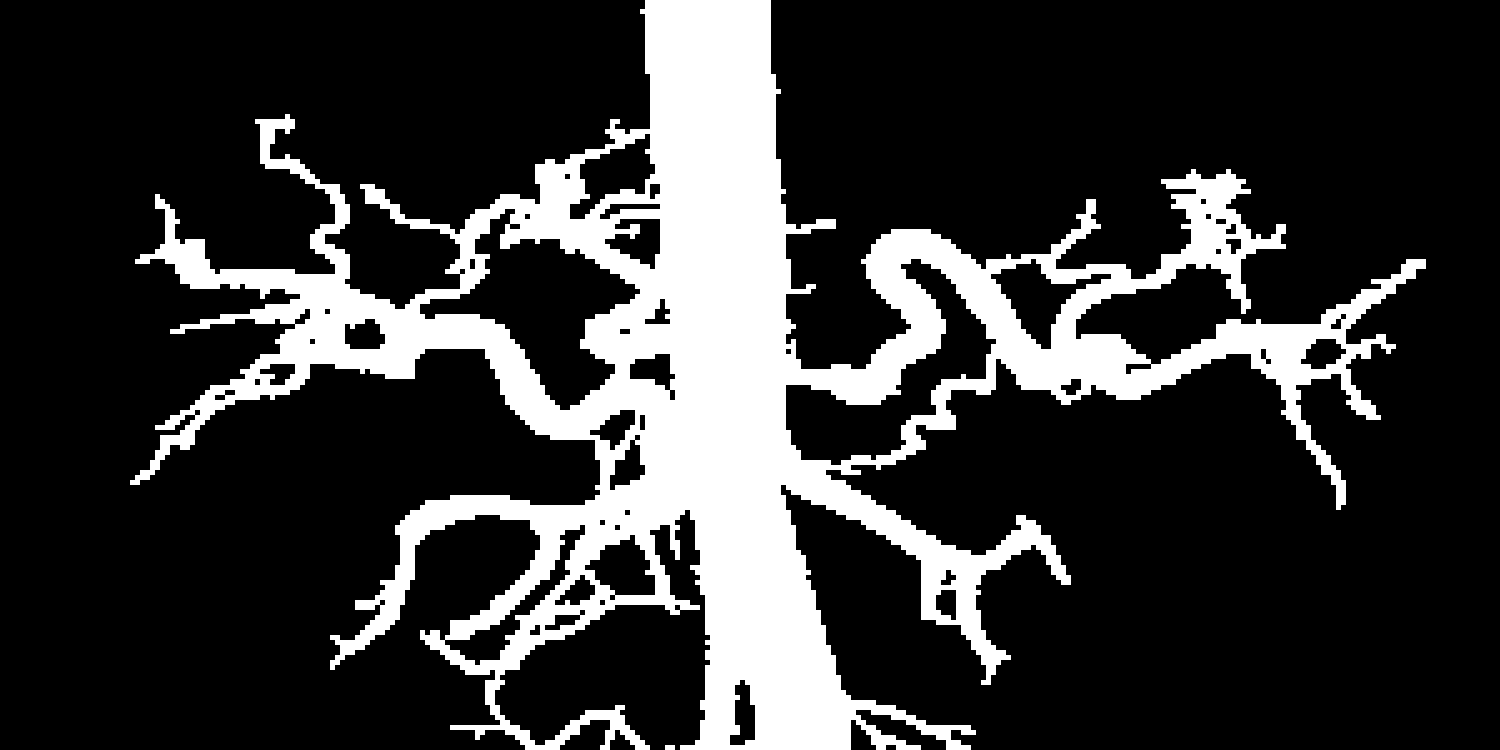

Given a binary 2D annotation of a MIP , we map the foreground pixels in A to the original 3D image space. This is achieved by using the first and last coordinates where the maximum intensity is observed along any projection ray. Owing to the fact that the vessels in the abdominal cavity are relatively sparse in 2D projections and most of the occluding tissue is removed in postprocessing, this step results in a fairly complete surface of the vessel tree. Furthermore, we can partially fill this surface volume, resulting in a 3D depth map , which is a partial segmentation of the vessel tree. We use the 2D annotations as well as the depth map to train a 3D segmentation network in a weakly supervised manner.

An overview of our method is presented in Figure 1. In the following, we describe these components and how they are combined to train a 3D segmentation network in more detail.

Depth information.

We can view MIP as capturing the intensity of the brightest pixel along each ray , where . Along each projection ray, we denote the first and last coordinates which have the same intensity as the MIP to be the forward depth and backward depth . This information can be utilized for the following: (1) enhancing the MIP visualization, or (2) providing a way to map pixels from the 2D MIP back to the 3D space (depth map). The reason why the maximum intensity is achieved multiple times along a ray is because our images are clipped, which removes a lot of the intensity fluctuations.

Depth-enhanced MIP.

We encode depth information into the MIPs by combining the MIP with the forward and backward depth respectively, in order to achieve better depth perception during annotation: defines the forward projection, while defines the backward projection. Figure 2 showcases (a) forward and (b) backward depth encoded MIPs.

Depth map generation.

Foreground pixels from the 2D annotations are mapped to the 3D space by combining a 2D annotation with the forward and backward depth, resulting in a 3D partial vessel segmentation: {topbot}

For each foreground pixel in the annotation A at location , we label and as foreground pixels in .

If the fluctuation in intensity between and along the ray is below a certain threshold in the source image I, the intermediate pixels are also labeled as foreground in .